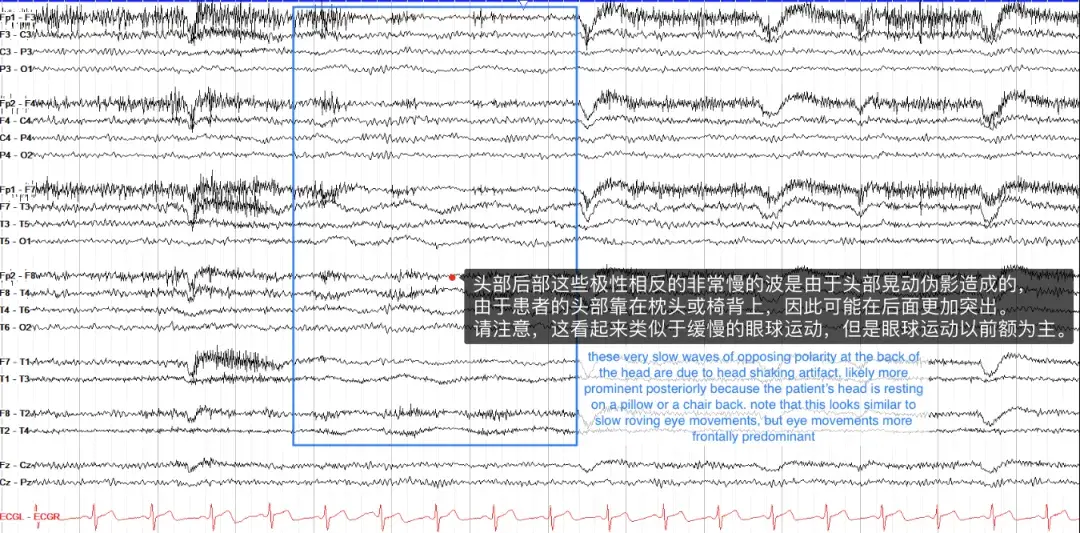

运动伪影具有多种外观,通常看起来混乱、高强度活动,不模仿任何实际的大脑模式。其中,摇头伪影可能稍微棘手一些,其特点是缓慢、低幅度的活动,如果患者将头枕在枕头上,这种活动通常在后方更为明显。它看起来类似于困倦时的眼球游动,但眼球运动是在前导联中。